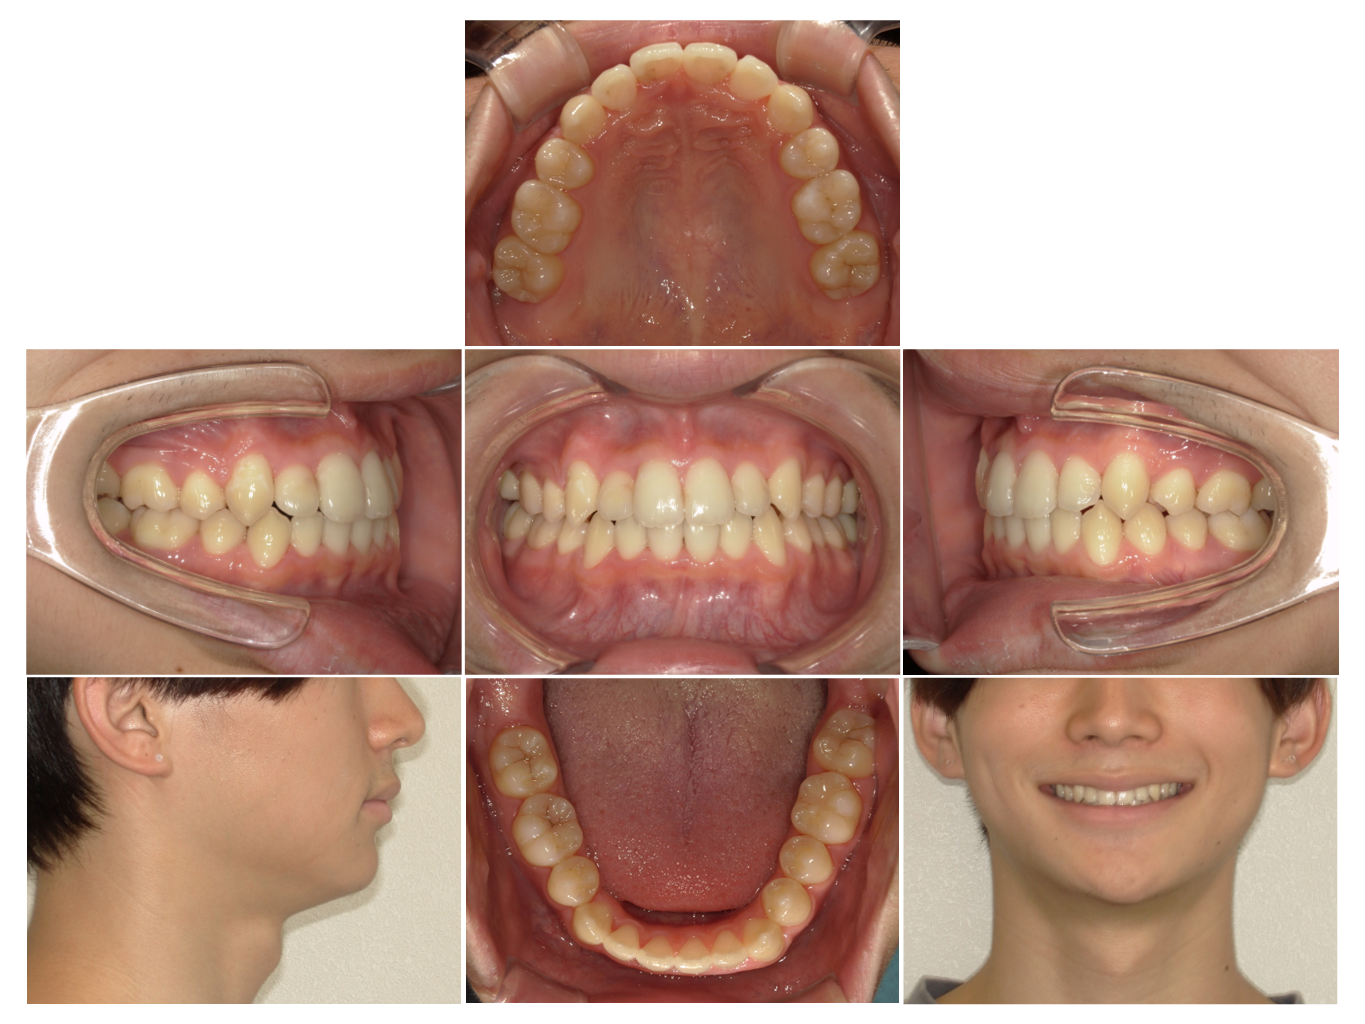

症例4

| 来院時の主訴 | 全体的なガタガタ |

| 医院での対応や適用装置 | マウスピース矯正装置を使用して主訴である |

| 通院期間 | 11ヶ月 |

| 通院回数 | 5回 |

| 治療費用総額 | 852,500円(税込) |

| リスクと副作用 | 矯正治療による歯の移動に伴う痛み、歯根吸収、虫歯 |